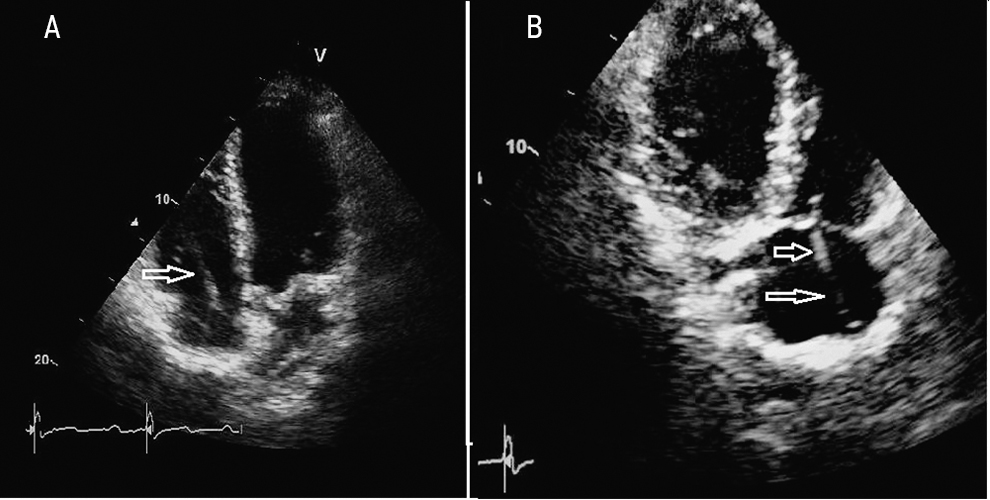

A month after discharge, fever recurred, and this time, in addition to the symptoms already listed earlier, there was hyperemia and soreness in the area of the pacemaker bed. In early December 2018, the patient was hospitalized with a diagnosis of “pacemaker bed abscess”. In control TTE and TEE, no reliable vegetation was found in the projection of electrodes, valves, and free endocardium. There was only uneven compaction and thickening of some areas of the electrode (Fig. 2). Staphylococcus Aureus was re-isolated in blood cultures. The therapy was carried out with vancomycin (1 g) with gentamicin (80 mg) for 25 days. After sanitation of the abscess and with antibiotic therapy, regression of all symptoms was again noted, with complete normalization of blood counts.

Fig. 2. Echocardiograms of patient A. Arrows indicate uneven compaction and thickening of the electrode sections located in the right chambers of the heart. Reliable formations in the projection of the electrodes are not determined. A — Four-chambered apical section; B — Modified three-chambered apical section (through the inflow sections of the right ventricle).